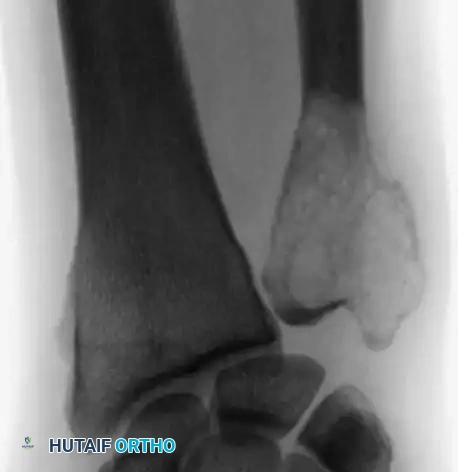

Advanced Reconstructive Modalities and Distal Extensions

While proximal humeral resections dominate shoulder oncology, tumors extending into the humeral diaphysis or distal humerus require equally complex limb salvage strategies. Total humeral replacement or distal humeral megaprostheses are viable options when the radial nerve can be preserved or grafted.

Intraoperative Imaging and Margin Assessment

Continuous intraoperative assessment using fluoroscopy and frozen section pathology is mandatory. The following images demonstrate various stages of complex upper extremity resections, allograft preparations, and prosthetic implantations across the humerus and elbow joint.

Distal Humerus and Elbow Reconstruction

When tumors involve the distal humerus, resection often requires sacrifice of the collateral ligaments and the articular surface of the elbow. Reconstruction is typically achieved using a linked, semi-constrained total elbow arthroplasty designed for oncologic defects.